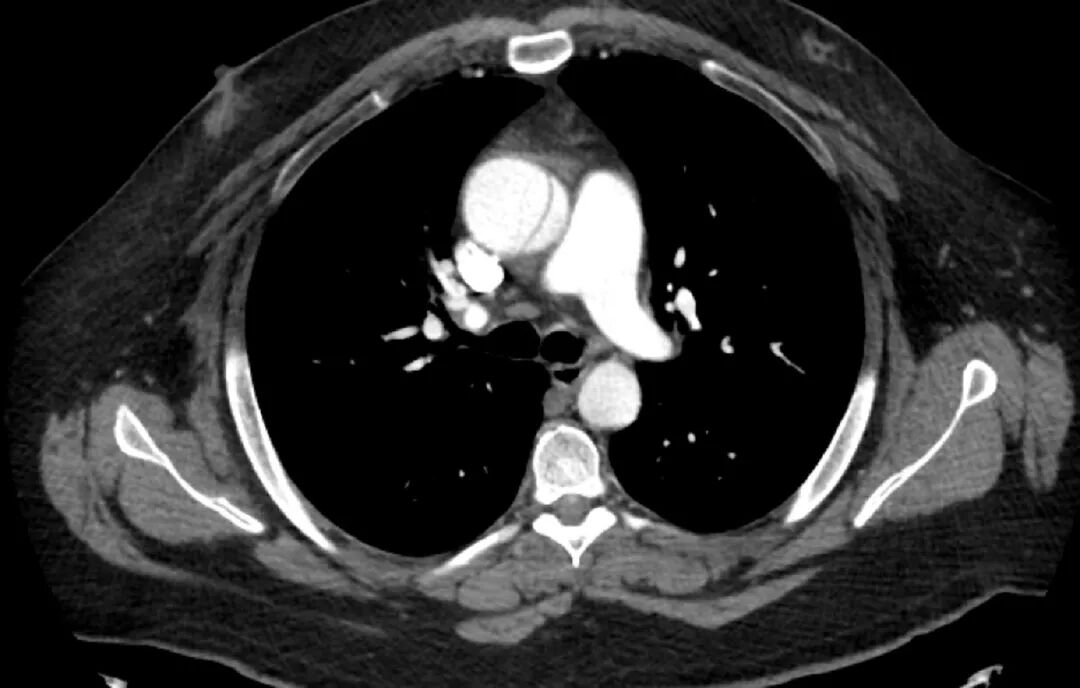

图 1.胸部、腹部和骨盆 CT 血管造影:轴位视图

CT血管造影显示升主动脉夹层动脉瘤,Stanford A型,可见内膜片(特征性征象);瓦氏窦受累,主动脉直径达 7 cm;